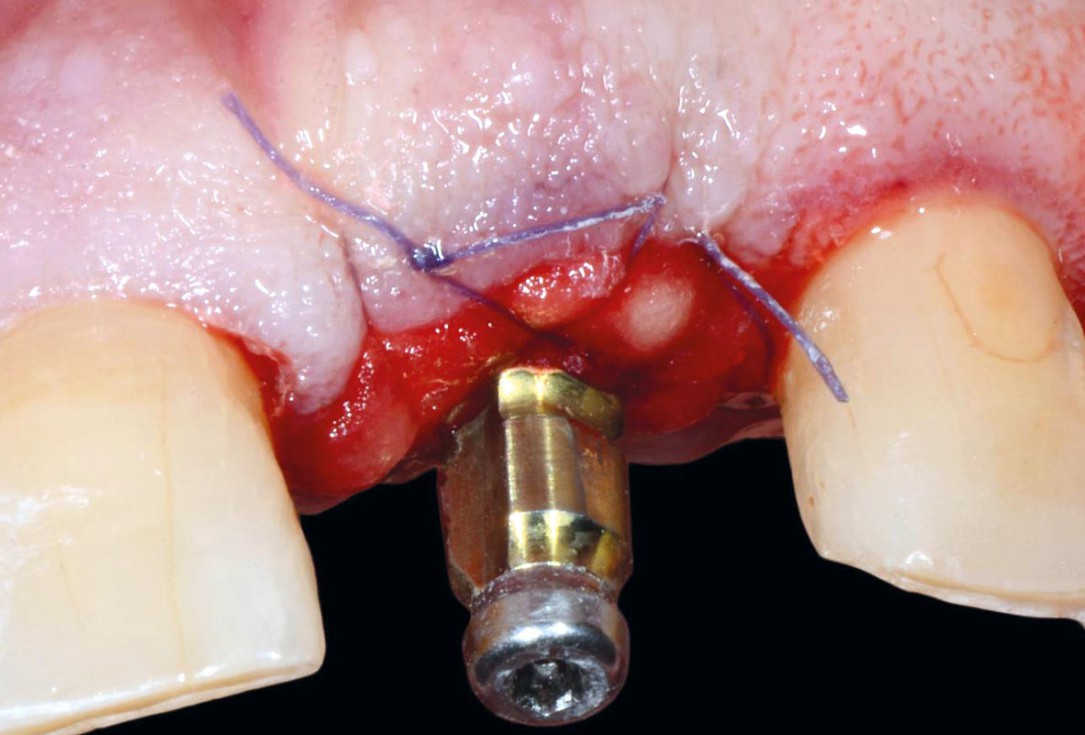

Initial situation pre-op: Central incisors with mobility 3

Initial clinical situation - Central incisors with dental destruction and periapical pathology